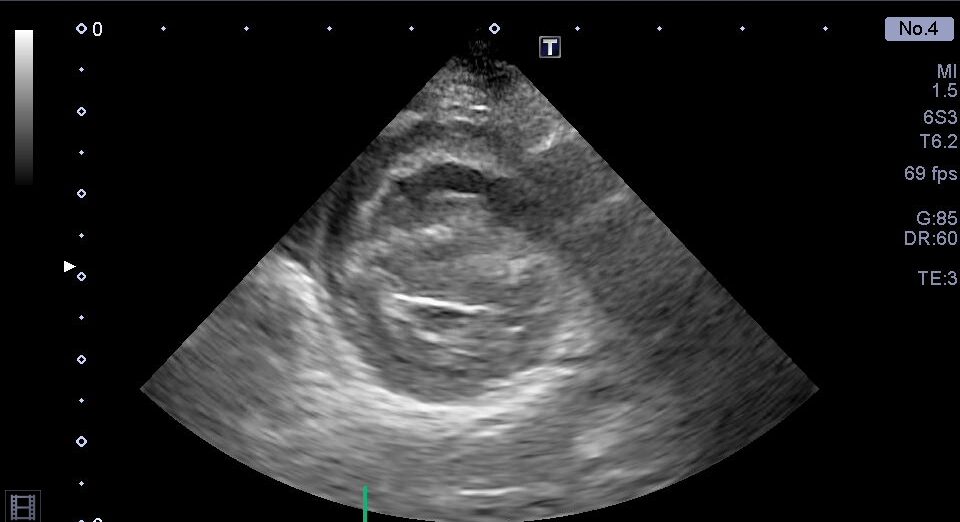

右心系の拡大

心室中隔の扁平化

肺動脈血流の加速時間短縮

重度の三尖弁逆流

胸部超音波検査では、上記のような肺高血圧症による心臓の変化が認められました。